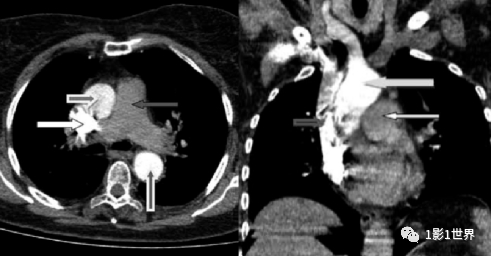

肺动脉CTA扫描:轴位CT图像显示上腔静脉、升主动脉和降主动脉造影剂强化,而肺动脉主干相对密度较低。

这种伪影可导致不确定的检查结果或被误解为肺栓塞